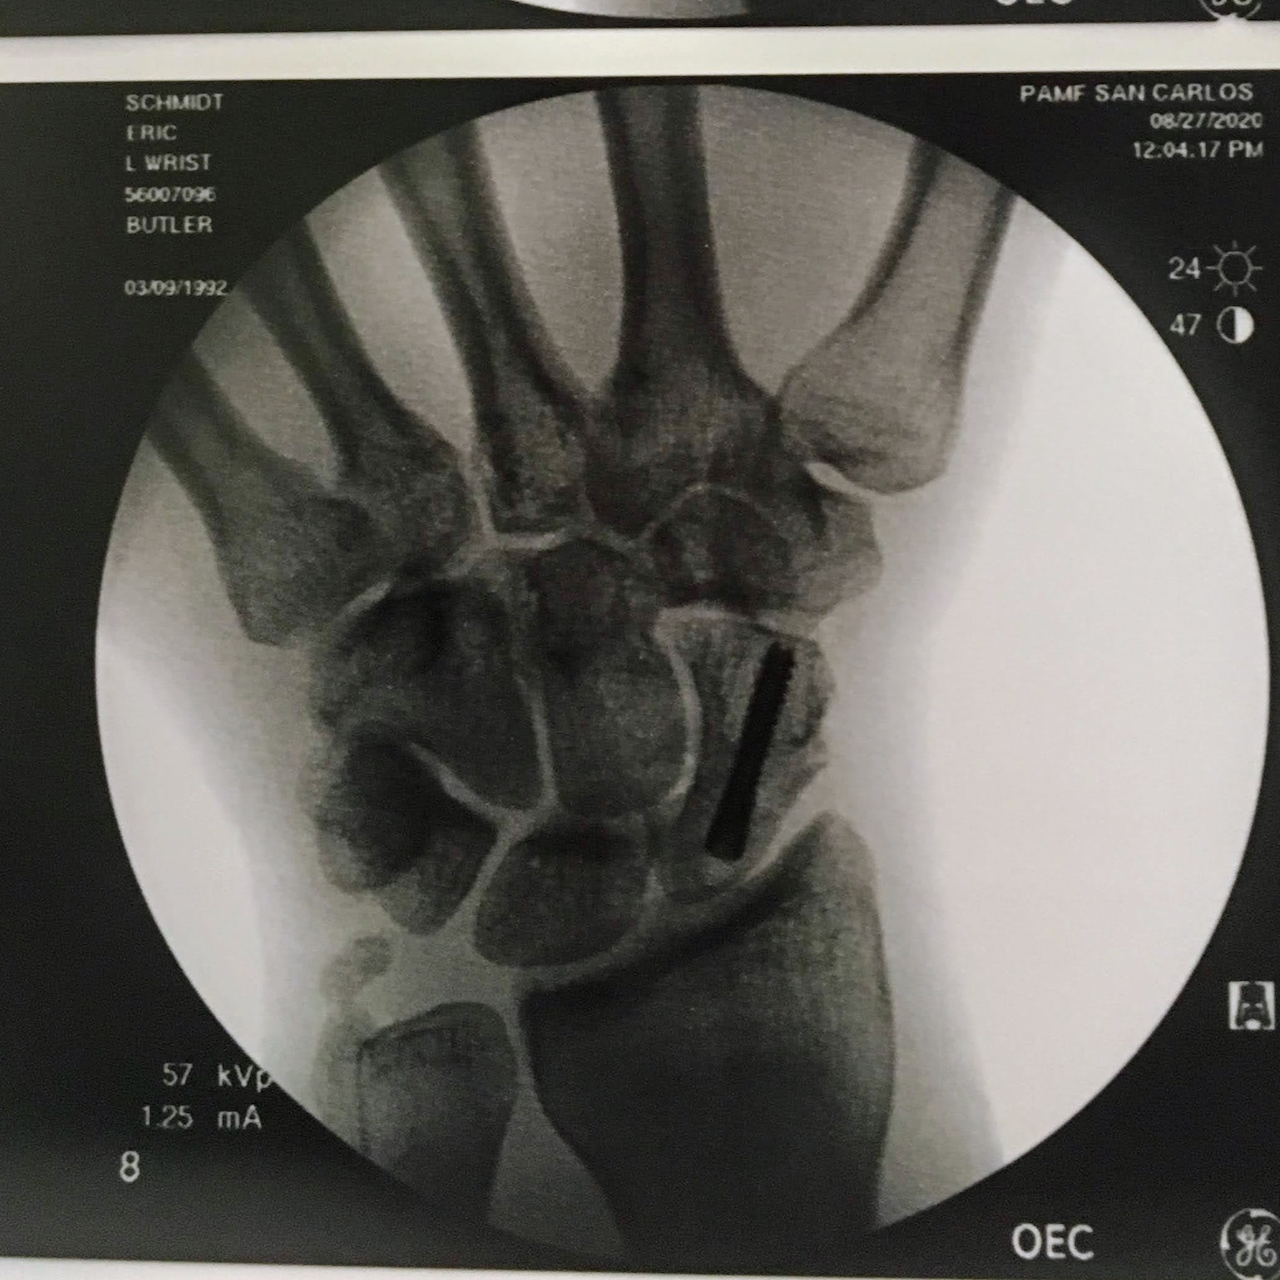

Unfortunately one new motorized vehicle in

his life (the new motorcycle) helped him to

break his wrist and get rather scraped up

He is now the second in the Schmidt family

to have hardware in a joint! (Lisa has more.)